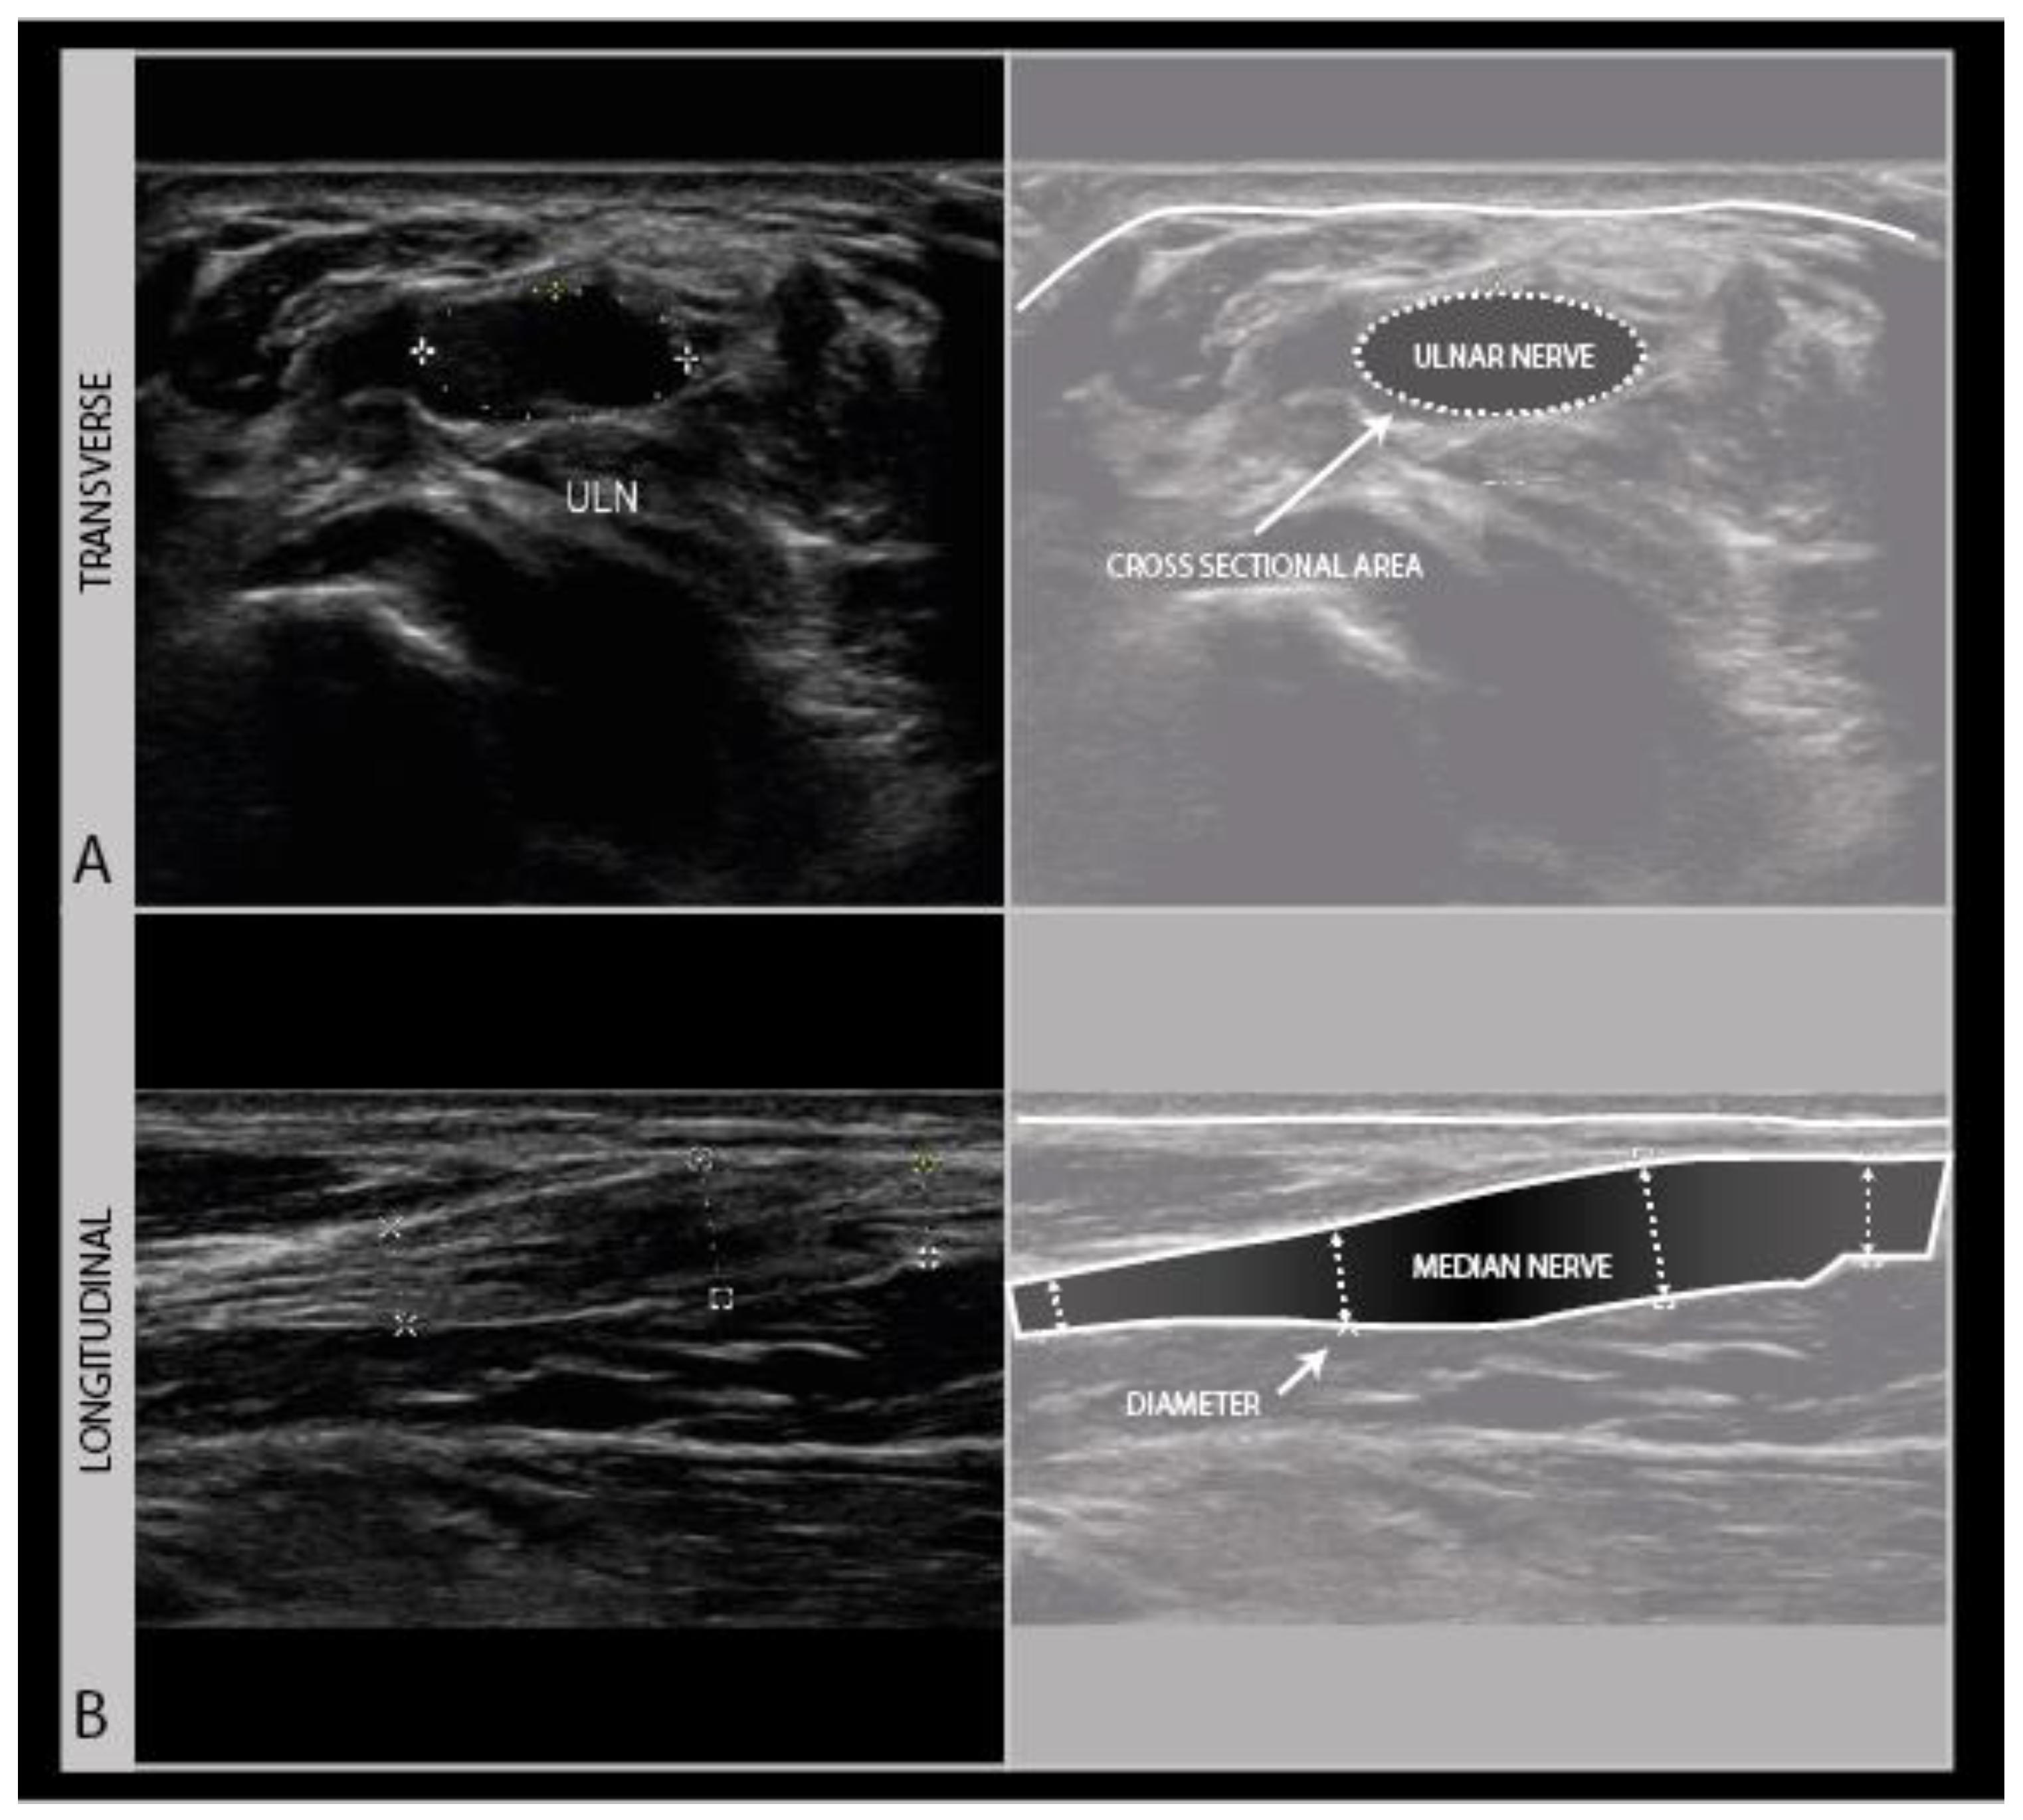

To assess the nerves for abnormality, it is strongly advised to scan the nerve all the way along its accessible length, looking for sudden changes in size or appearance. When an abnormality is found, it is advisable to also twist the probe 90° around and make a longitudinal image of the lesion site. When measuring neuroma sizes, placing several diameter markers proximal, at and caudal to the lesion site may be helpful (Figure 3).

Figure 3.

Image examples of transverse cross-sectional area (CSA) (A) versus longitudinal diameter measurement (B). A: distal ulnar neuroma; B: distal median nerve neuroma (adult male with a crush injury of the distal forearm). ULN = ulnar nerve.

Longitudinal images are not very good for the identification of the anatomical location, but they are more intuitive for looking at pathology by referring physicians (or patients). It is advisable to annotate images with sparse text to indicate the site, including a nerve name abbreviation such as “MED” for the median nerve, and an indicator for left/right, distal/proximal, etc.). For any nerve that could require surgical intervention, it is recommended to measure the site of abnormality in reference to a recognizable anatomical landmark (e.g., “5 cm distal from the intermalleolar line, 2 cm lateral from the midline” etc.). We strongly recommend making a short ultrasound video scanning from the proximal across a lesion site to a distal one, as ultrasound videos are much easier to interpret afterwards than still images. Finally, the images should be saved to a network location or printed to be saved with the patients’ health records.